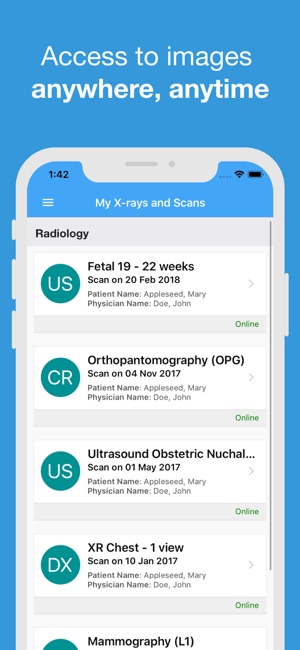

Having immediate access to X-rays and scans may give doctors and other health professionals, such as physiotherapists and chiropractors, a more complete picture of your relevant medical history.

You might want to look at your images again, when you are not at your doctor’s surgery. Or, you may wish to share a special scan with family or friends.

X-rays and scans are an important part of your medical history in the same way as previous medications and blood tests are important. Having immediate access to X-rays and scans may give doctors a more complete picture of your relevant medical history.